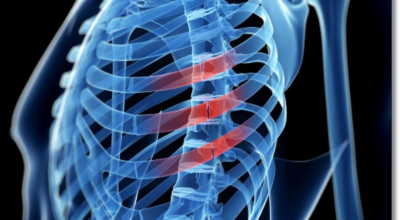

흉추와 복장뼈를 관련해서 가슴 전체를 둘러싸고 있는 가슴우리(흉강)을 형성하는 긴 곡선의 뼈를 말합니다. 갈비뼈는 폐, 심장 등 내부 가슴 장기들을 지켜주며 가슴우리의 팽창과 수축으로 호흡을 도와줍니다. 우리 몸은 총 12쌍의 갈비뼈를 가지고 있답니다.

1~7번 갈비뼈는 복장뼈와 직접 관절로 연결되어 있어 참갈비뼈라고 하며, 8~12번 갈비뼈는 거짓 갈비뼈라고 하는데 거짓 갈비뼈 중 8, 9, 10번 갈비뼈는 또다른 연골을 통해 복장뼈와 연결되어 있으며 나머지 11~12번째 갈비뼈는 뜬갈비뼈로 복장뼈와 연결되어 있지 않습니다.